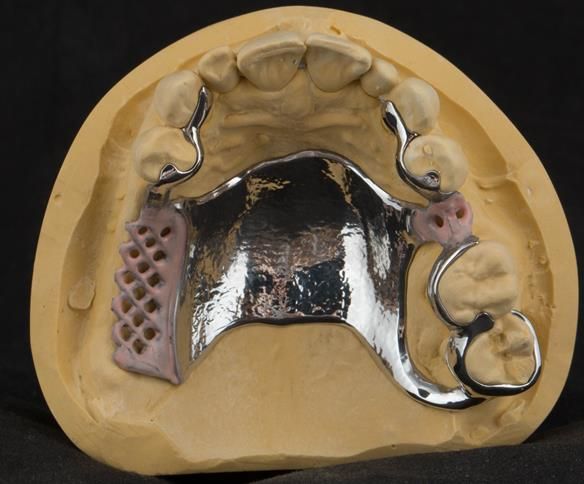

This newsletter describes in step by step detail Angela's transition through immediate partial dentures to crown supported definitive metal based dentures.

The clinical situation and treatment process is shown in detail below with photographs. I (Finlay Sutton) provided the clinical work and Rowan Garstang provided the technical work.